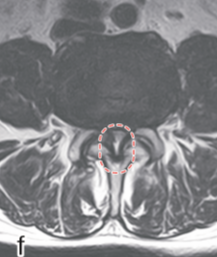

画像所見

レントゲン像 MRI像